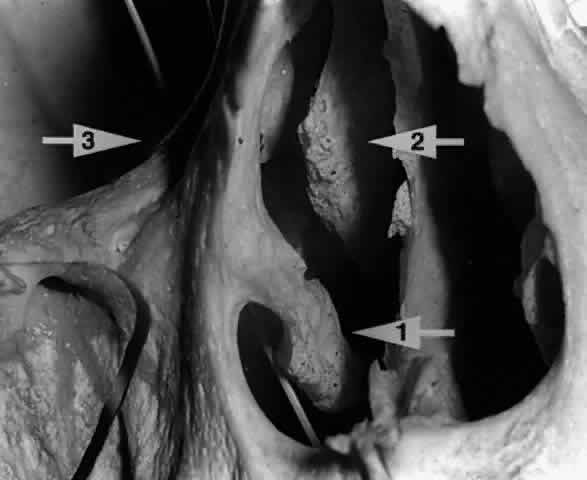

The parenchyma of the gland is made up of small lobules separated by a fine connective tissue network. The lacrimal gland has approximately 12 secretory ducts (Fig. 7), which average 0.66 mm in diameter and 2.31 mm in length.4 Two to five of them originate from the orbital lobe and six to eight from the palpebral lobe. The ductules from the orbital portion of the lacrimal gland pass through the parenchyma of the palpebral lobe before exiting into the superotemporal portion of the conjunctival fornix 4 or 5 mm above the upper border of the tarsus. One or two may open near the lateral canthus.5 Excision of the palpebral lobe may therefore interrupt drainage from the orbital lobe as well.

Fig. 7. Secretory ducts (arrow 1) of the right lacrimal gland (arrow 2) are seen passing to the palpebral conjunctiva (arrow 3). (Courtesy of James Sanderson, MD, Orkan Stasior, MD, and George Stasior, MD)

Sanderson and Stasior4 found islands of “peripheral” lacrimal glandular tissue below the lateral canthus unassociated with the main gland in 60% of cadaver specimens (Fig. 8). These peripheral islands of glandular tissue were found less commonly in or above the lateral canthal tendon.

Fig. 8. “Peripheral” lacrimal gland lobules (arrow 1) are seen below the right lateral canthus (arrow 2) and separate from the palpebral lobe of the lacrimal gland (arrow 3). (Courtesy of James Sanderson, MD, Orkan Stasior, MD, and George Stasior, MD)